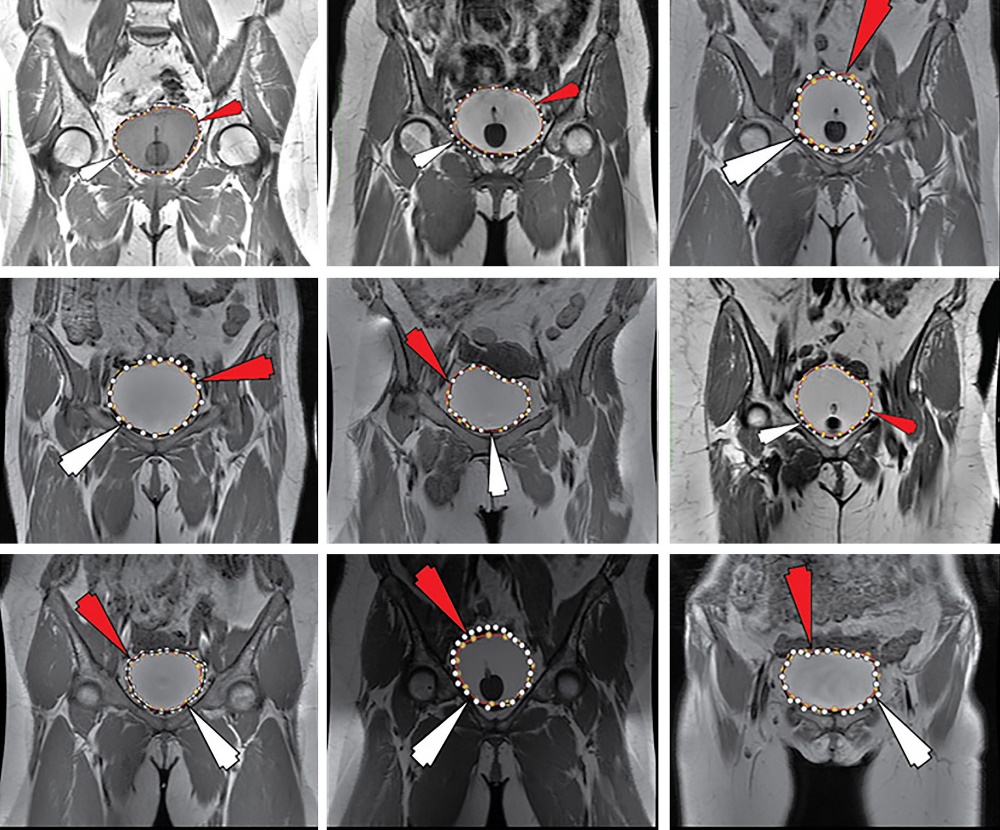

The accuracy of our method was determined by comparing positions and closest edges between the technologist-/radiologist-specified edge points. All intermediate steps are shown for the remaining eight patients are shown in Figure 3 through Figure 10. The results from the machine learning produced 6400 control points to be evaluated (in a subset across all dynamic series and patient sets in our evaluation). As previously stated, there are complex challenges associated with segmenting organs in the abdomen and pelvis (Figure 1B). With the application of ML, accuracies for the training set=90.0% validation set= 91.6%, and test set=90.73% were improved. This corresponded to cross-validation error of the training set=2.93, validation set=8.22, and testing set=8.254, in which lower numbers are considered better. The ML procedure took 52 epochs to achieve convergence, which occurred in ~28 seconds across all our data points.

Figure 3Illustration of the second patient with intermediate steps (the first patient was shown in Figure 1).

Figure 4Illustration of the third patient with intermediate steps.

Figure 5Illustration of the fourth patient with intermediate steps.

Figure 6Illustration of the fifth patient with intermediate steps.

Figure 7Illustration of the sixth patient with intermediate steps.

Figure 8Illustration of the seventh patient with intermediate steps.

Figure 9Illustration of the ninth patient with intermediate steps.

Figure 10Illustration of the tenth patient with intermediate steps.

In Figure 11, we illustrate the results of the Receiver Operating Curves (ROC) for both the training and validation sets. Note that as the ROC curves shift upwards, these shapes for our ROC curves appear to indicate adequate performance across classes. The training, validation, test and overall confusion matrix are shown in Figure 12. Figure 13 illustrates all ROI data for all patients on a single figure. Figure 14 illustrates zoomed images of the ground truth and ML segmented ROIs for these patients. The red arrow is the computer-generated result, while the white arrow is the expert-generated result.Additionally, we were interested in whether the technique achieved an overall 65.2% time reduction over manual segmentation alone, as the technologist/radiologist may do some fine-tuning. However, when using the ML method, 80.0% of slices had moderate to substantially strong placement along the boundary (high levels of agreement with the radiologist delineation were in the top 37.4% of this group, without large corrections). To validate the results, we applied the Jaccard Similarity Measure, which we report to have a mean score of 0.933 (95% Confidence Interval 0.923, 0.944) with the highest possible value for complete agreement of 1.00 for that measure as shown as a distribution in Figure 15.

Figure 13Results for all 9 patients. The red arrow is the computer-generated result, while the white arrow is the expert-generated result.